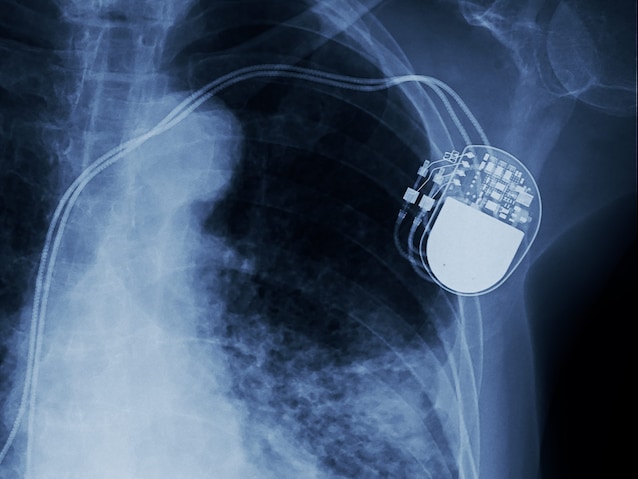

Plant Pacemaker og hjertestartere: Forskjeller

Defibrillering er også til stede i funksjonen av Kunstig pacemaker. Imidlertid, mens jeg Pacemakers gir kontinuerlige impulser For å kompensere for en permanent kronisk defekt – for eksempel en bestemt del av hjertet som ikke lenger er i stand til å trekke seg sammen uavhengig – i Implanterbare hjertestartere kommer bare i drift i tilfelle en nødsituasjonnår de oppdager potensielt dødelig arytmi.